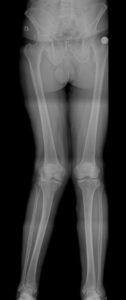

São deformidades do joelho no plano coronal, aquelas observadas de frente.

- Joelho varo (genu varum): pernas arqueadas, cambotas

- Joelho valgo (genu valgum): joelhos em X

Essas alterações modificam a forma como o peso do corpo é distribuído sobre o joelho. Ou seja, um joelho com deformidade, não distribui a carga uniformemente causando a sobrecarga da cartilagem articular em algum compartimento. Assim, no joelho varo, há uma sobrecarga no compartimento medial (interno) e no joelho valgo, no compartimento lateral (externo).

7. Como é feito o diagnóstico?

O diagnóstico é realizado por meio de:

- Avaliação clínica

- Análise do alinhamento dos membros

- Radiografia panorâmica em carga

Esses exames permitem identificar o grau da deformidade e indicar o melhor tratamento.